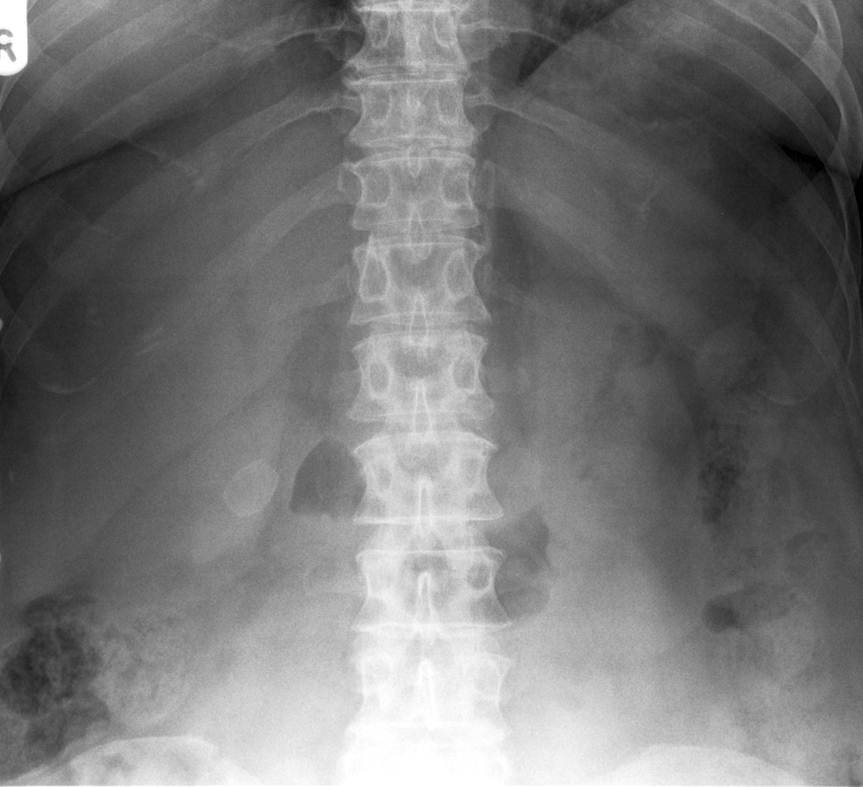

what does this image show?

Dilated Colon - Sigmoid Volvulus

This occurs in cases of long-standing chronic constipation where patients develop a large, elongated, relatively atonic colon, particularly in the sigmoid segment. It is often referred to as acquired or idiopathic megacolon. In sigmoid volvulus, a large sigmoid loop full of faeces and distended with gas twists on its mesenteric pedicle to create a closed-loop obstruction. If uncorrected, venous infarction leads to perforation and faecal peritonitis.